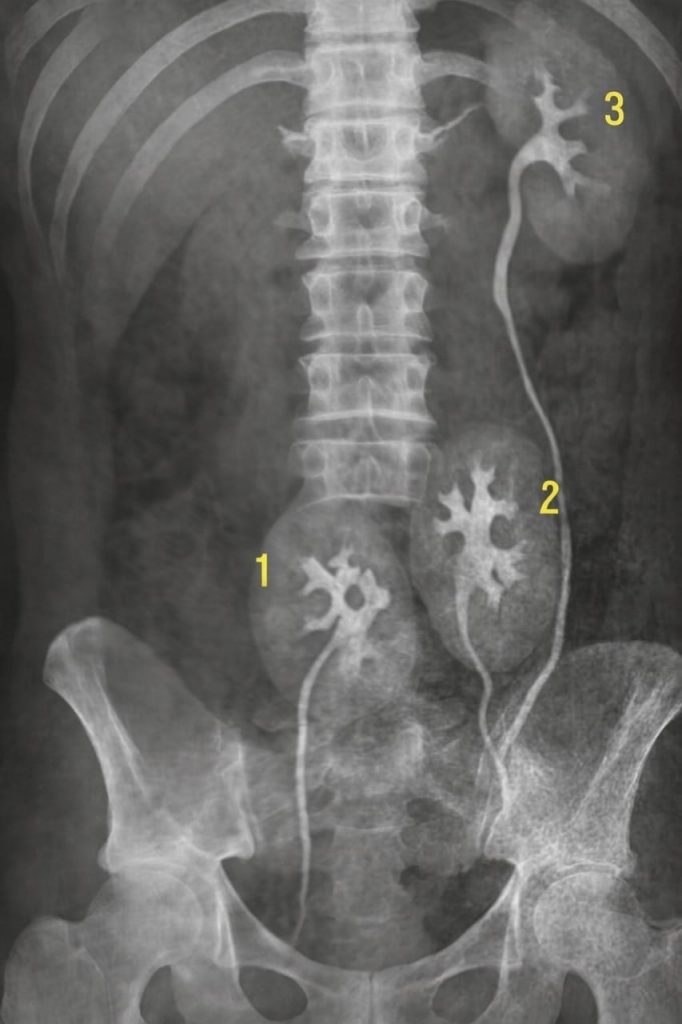

Trois reins.

Un « en trop ». Parfaitement formé. Totalement fonctionnel.

Sur un ancien cliché médical, un homme — presque son double — apparaissait avec la même anomalie encerclée au crayon.